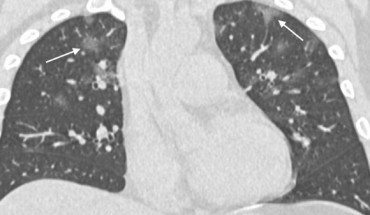

In a retrospective case series, an international team of radiologists has reviewed chest CT scans of 21 symptomatic patients from China infected with the 2019-nCoV coronavirus. Typical CT findings included bilateral pulmonary parenchymal ground-glass and consolidative pulmonary opacities, sometimes with a rounded morphology and a peripheral lung distribution. Notably, lung cavitation, discrete pulmonary nodules, pleural effusions, and lymphadenopathy...